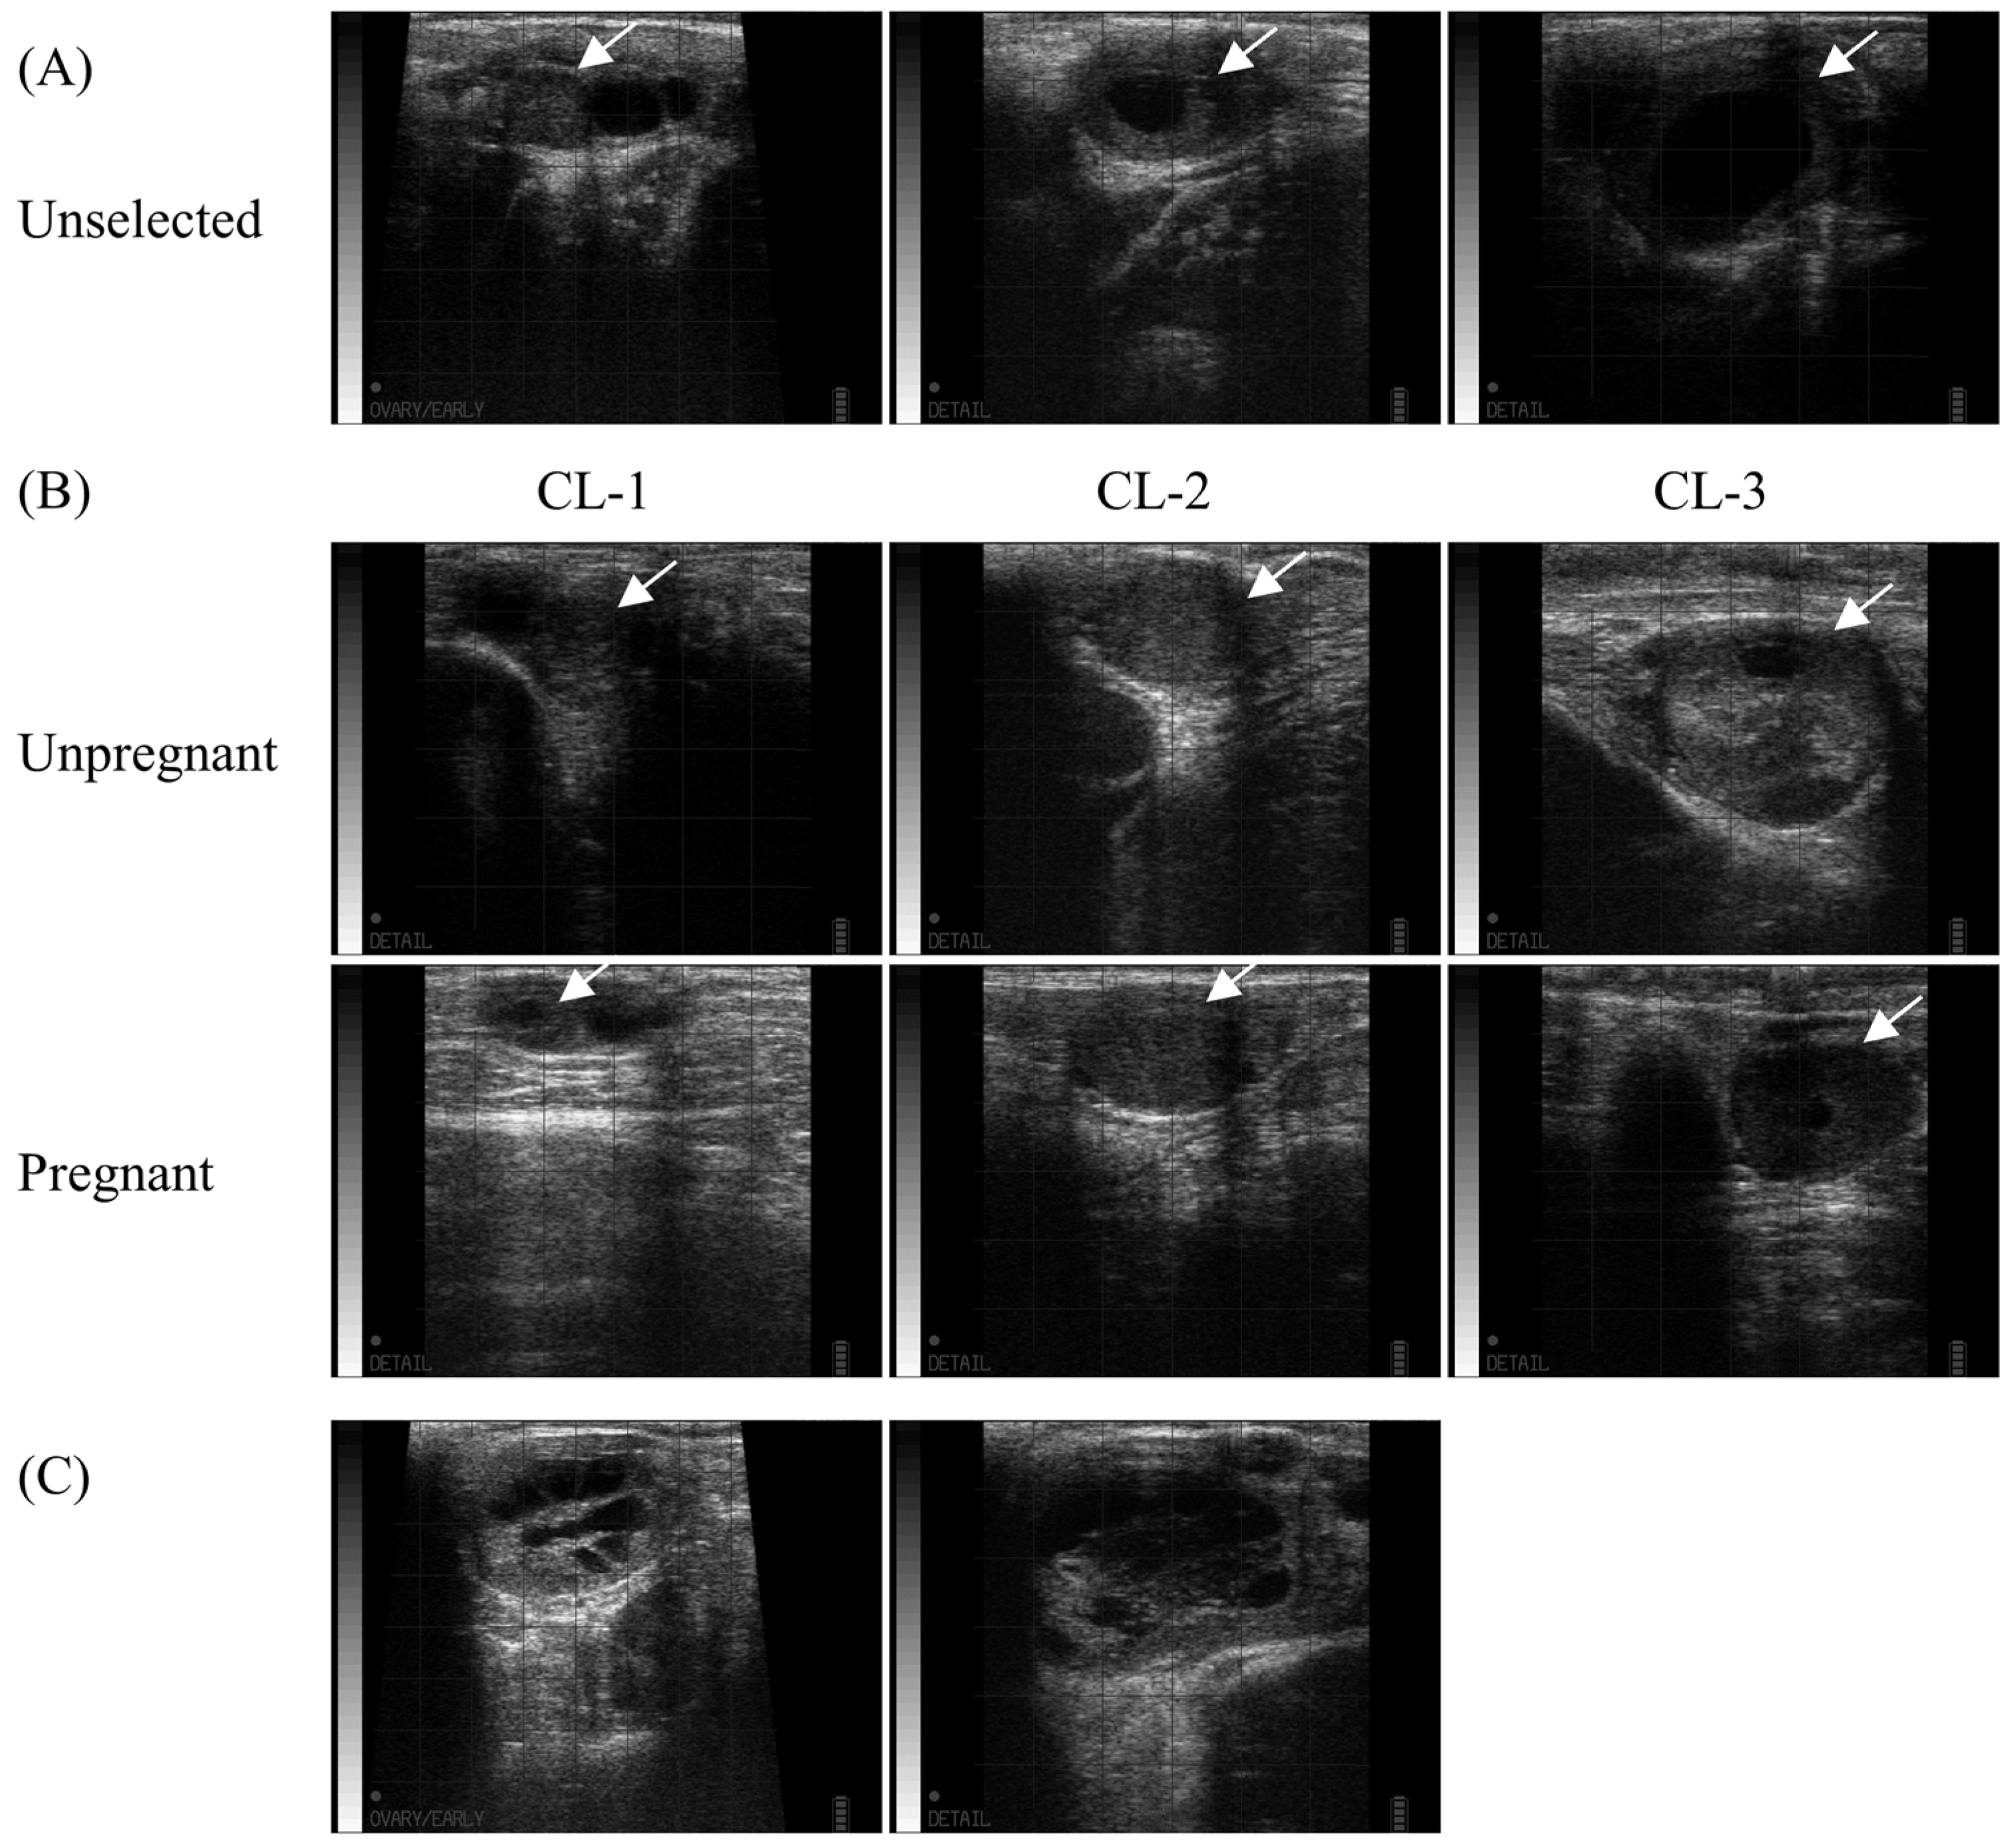

2.2. Recipient Evaluation

| CL-1 | CL-2 | CL-3 | Total | |

|---|---|---|---|---|

| P4-1 | 26.7% (4/15) | 46.2% (12/26) | 16.7% (1/6) | 36.2% (17/47) a |

| P4-2 | 25.0% (1/4) | 71.4% (15/21) | 40.0% (2/5) | 60.0% (18/30) a |

| P4-3 | 33.3% (1/3) | 60.0% (9/15) | 33.3% (1/3) | 52.4% (11/21) a |

| Total | 27.3% (6/22) a | 58.1% (36/62) b | 28.6% (4/14) ab | 46.9% (46/98) |